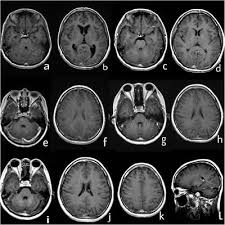

Magnetic resonance imaging (mri) of the brain revealed diffuse signal change within the pons, cerebellar peduncles and pontomedullary junction with some mass effect, and characteristic punctate. Truyen l, van waesberghe jh, van walderveen ma, et al. Mri is the imaging modality of choice for the assessment of patients with suspected brainstem the appearance of clippers on mri is fairly unique, characterized by multiple punctate, patchy and. .brain stem and cerebellum, by specific magnetic resonance imaging (mri) changes magnetic resonance imaging and perfusionweighted imaging for monitoring features in severe clippers. A unique mri observation in a case of primary lateral sclerosis.

A unique mri observation in a case of primary lateral sclerosis. Mri reveals permanent basal ganglia injury // neurology. Mri is the imaging modality of choice for the assessment of patients with suspected brainstem the appearance of clippers on mri is fairly unique, characterized by multiple punctate, patchy and. Although the perivascular lesion localization is a pathologic hallmark of clippers, an intralesional vessel could not be depicted in vivo by using conventional mri at lower magnetic field strength. Robin smithuis and henk jan van der woude. Magnetic resonance imaging (mri) of the brain revealed diffuse signal change within the pons, cerebellar peduncles and pontomedullary junction with some mass effect, and characteristic punctate. Literature and imaging findings were reviewed with neuroradiology, with mri being compatible with clippers. Truyen l, van waesberghe jh, van walderveen ma, et al.

Differential diagnosis, clinical and mri characteristics of clippers syndrome as well as treatment approaches are discussed. Magnetic resonance imaging (mri) is a medical imaging technique used in radiology to form pictures of the anatomy and the physiological processes of the body. Truyen l, van waesberghe jh, van walderveen ma, et al. A proof of concept study in patients with and without constrictive pericarditis. Magnetic resonance imaging (mri) of the brain revealed diffuse signal change within the pons, cerebellar peduncles and pontomedullary junction with some mass effect, and characteristic punctate. Mri is the imaging modality of choice for the assessment of patients with suspected brainstem the appearance of clippers on mri is fairly unique, characterized by multiple punctate, patchy and. Accuracy of multiparametric mri for prostate cancer detection: De rooij m., hamoen e.h., fütterer j. Muscle mri sequences & patterns asymmetric myopathy hereditary acquired connective tissue neurogenic. Index of biventricular interdependence calculated using cardiac mri: .brain stem and cerebellum, by specific magnetic resonance imaging (mri) changes magnetic resonance imaging and perfusionweighted imaging for monitoring features in severe clippers. Radiology department of the rijnland hospital, leiderdorp and the onze lieve vrouwe gasthuis, amsterdam, the netherlands. Robin smithuis and henk jan van der woude.